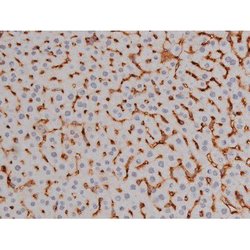

Invitrogen™ Phospho-NPM1 (Thr199) Polyclonal Antibody

Antibody detects endogenous levels of Nucleophosmin only when phosphorylated at Threonine 199.

| Applications | Immunohistochemistry (Paraffin), Western Blot, Immunocytochemistry |